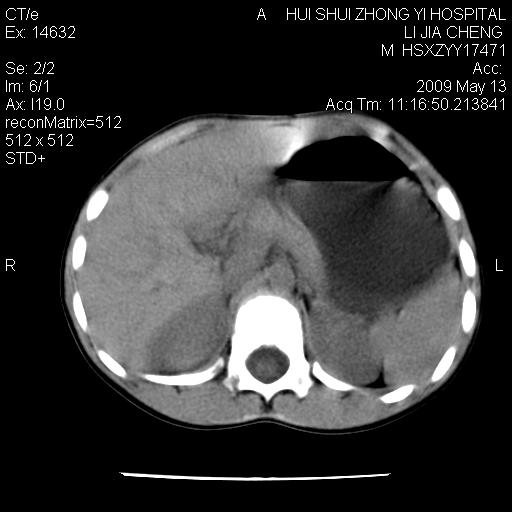

脂肪肉瘤可能性大,大血管边界不清,特别是腔静脉。不除外其他腹膜后肿瘤。

是不是有蛔虫哦,楼主图示块影前方肠管壁显著增厚,不除外慢性肠炎或肠壁占位,建议肠道准备后复查

来源于十二指肠水平部病变?建议行进一步检查。

肠管管壁均匀增厚,炎性可能

是小肠,壁稍厚可能是肠腔未很好充盈所致,腹部ct扫描未见明显异常。